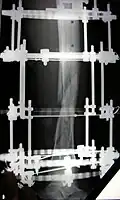

The photographs and radiographs illustrate the application and emplacement of an external fixator, an Ilizarov apparatus, to repair the open fracture of the lower left leg of a man. The photographs were taken four weeks after the patient fractured the shinbone (tibia) and the calfbone (fibula) of his left leg, and two weeks after the surgical emplacement of the Ilizarov apparatus to immobilise the leg and isolate the wound and fracture site to facilitate healing.

X-ray of the open fracture of the left leg; the external fixator was installed ca. 24 hrs. in hospital. -

X-ray of the open fracture site immediately after installation of the Ilizarov apparatus. -

X-ray of the fracture site and the emplaced apparatus, two months post-fracture; perspective 1-4. -

X-ray of the fracture site and the emplaced apparatus, two months post-fracture; perspective 2-4. -

X-ray of the callus forming at the fracture site, three months post-fracture; perspective 3-4. -

X-ray of the callus forming around the fracture site, three months post-fracture; perspective 4-4. -

X-ray perspectives of the callus-formation progress and healing of the fractured tibia and fibula bones, four months post-fracture.